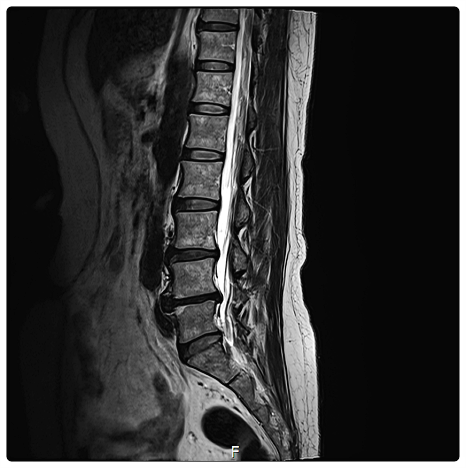

특히 요추 3, 4, 5번 부위에 통증이 집중된다면, 단순히 그 부위가 약해서라기보다

몸 전체 균형이 무너져 체중과 압력이 특정 지점으로 쏠리고 있을 가능성도 있습니다.

요추에 집중된 압력을 골반과 척추 전반으로 고르게 분산시키는 과정이 중요합니다.

특정 척추 마디에 과부하가 걸리지 않도록, 틀어진 골반 각도를 세밀하게 조정하는 것이 핵심입니다.

요추 3, 4, 5번 부근이 묵직하고 다리로 저릿한 감각이 이어진다거나,